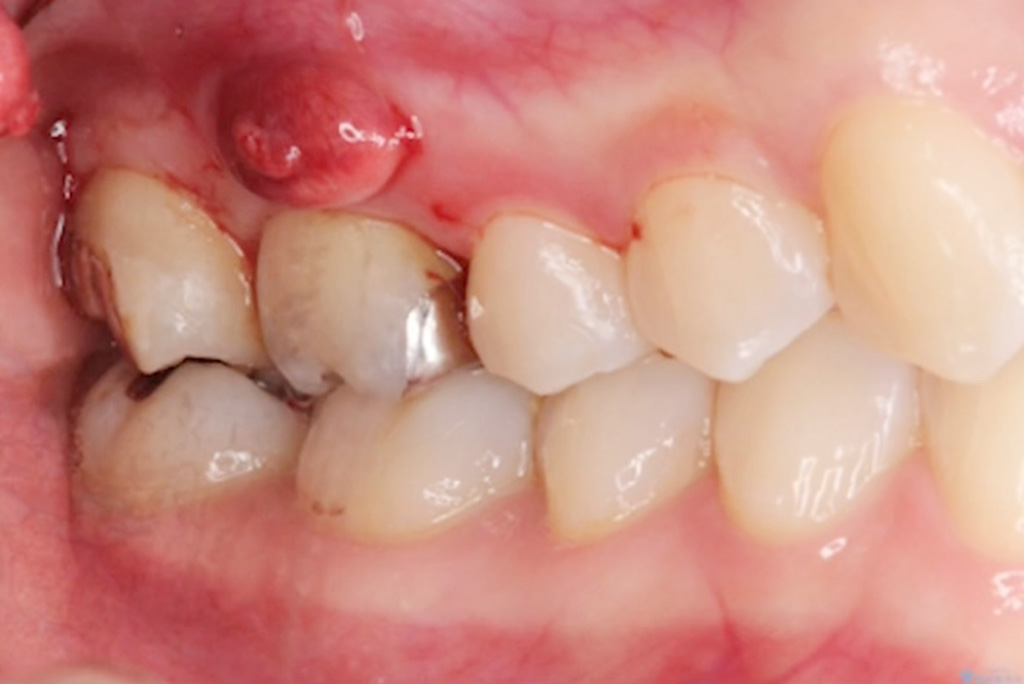

以前は、根尖病変などから

排膿している歯肉の開口部を

【フィステル(瘻孔)】と呼んでいました。

しかし現在は、

サイナストラクト(sinus tract)

という名称が使われることが増えています。

一方、歯科で見られる多くの排膿路は、

そのため、より正確な用語として

【サイナストラクト(排膿路)】が

用いられるようになりました。

臨床でも「フィステルですね」ではなく

「サイナストラクトが認められます」と

表現する流れになっています。